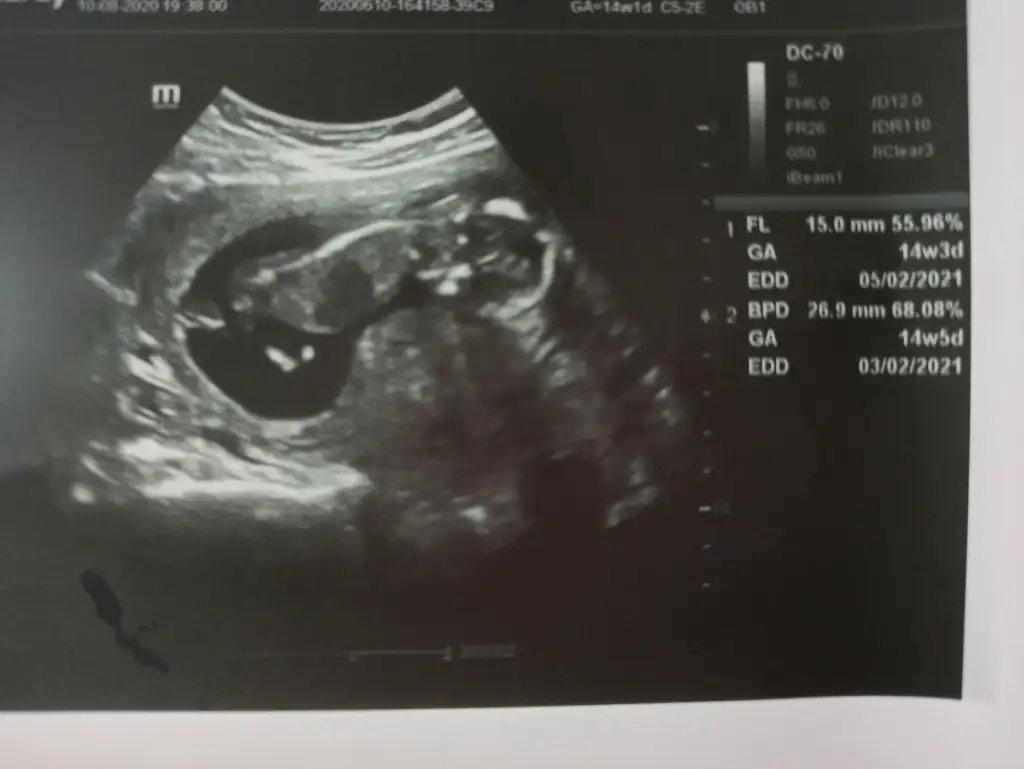

Merhabaaa ben de cinsiyetten emin olamayan doktor mağduruyum yardımcı olur musunuz

İlk fotoğraf 12+0

İkinci fotoğraf 12+3 (doktor çıkıntı gördüm sanki ama kesin değil dedi)

Üçüncü fotoğraf 14+2 (kız gibi dedi ama bakmaya devam ederken aaa pipi bu ama yine de emin olmak için 1-2 hafta sonra tekrar bakalım dedi)

son fotoğraf da gördüm dediği pipi